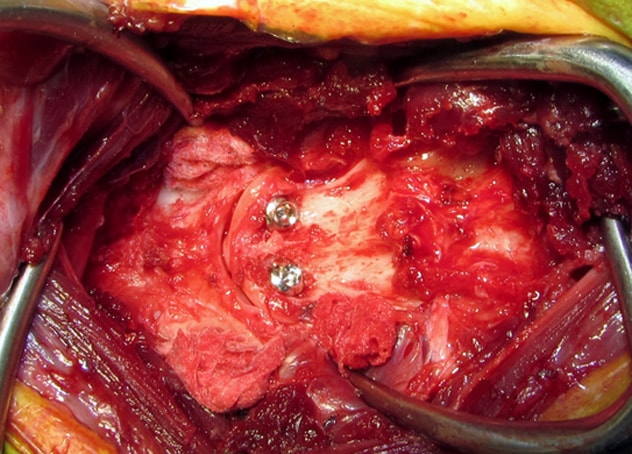

![]() 環椎と軸椎を固定するスクリューを2本挿入します。 |

![]() 次に環椎に2本、軸椎に2本のスクリューを挿入します。 |

![]() 環椎軸椎関節軟骨に上腕骨から採取した海綿骨移植を行います。 |

![]() 最後に外科用ボーンセメントで固定して終了です。 |